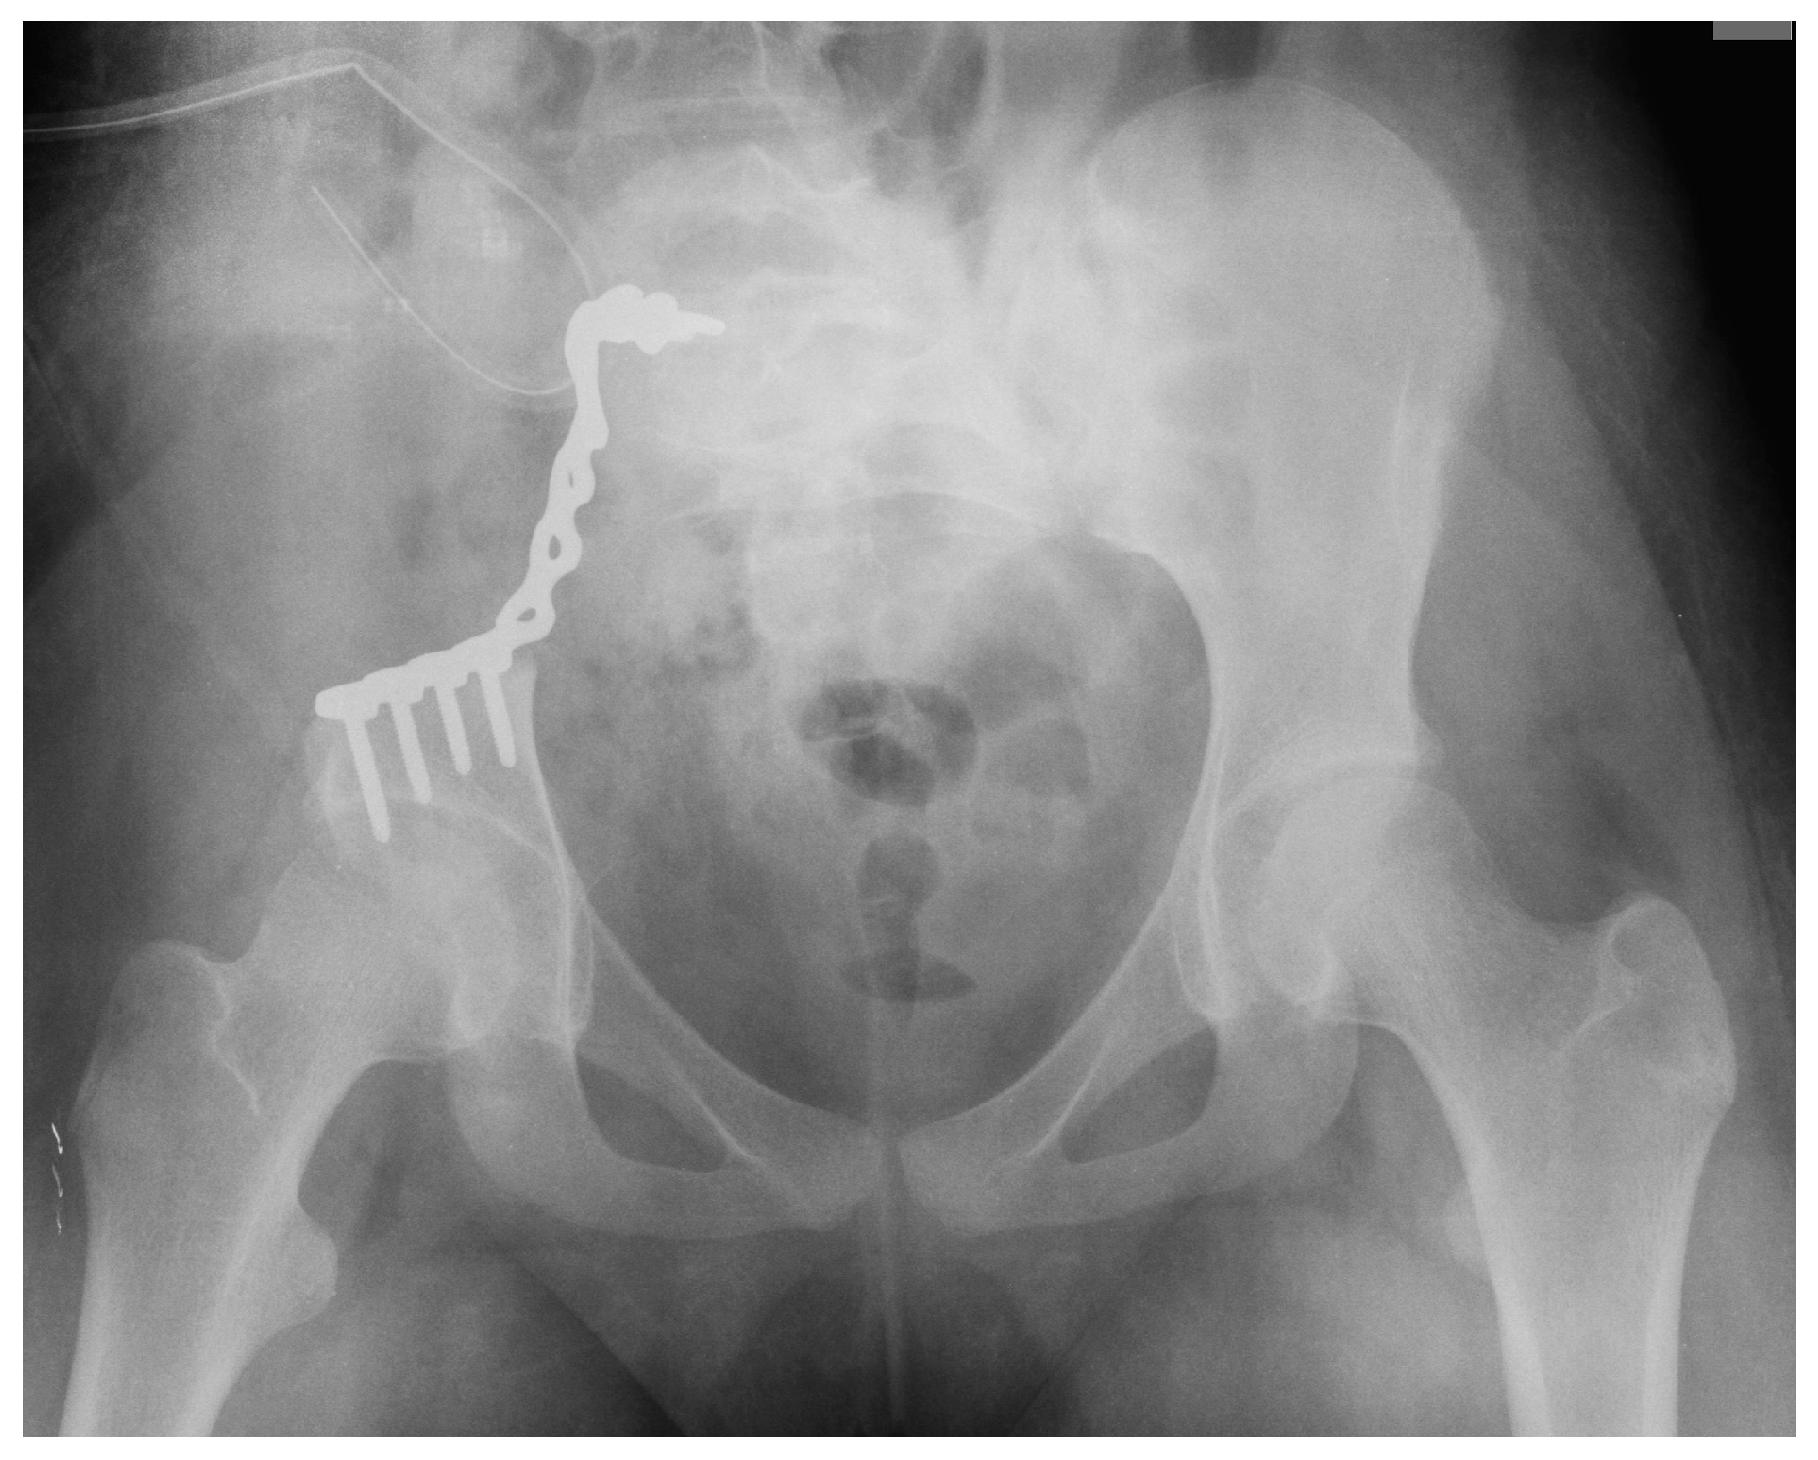

3.3.1. Pelvis Osteosarcoma